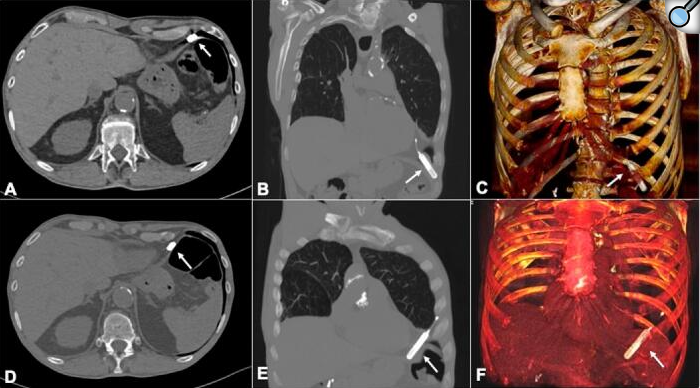

Introduction: Remote monitoring is recommended as part of the standard follow-up management strategy of ILRs. We report a case of asymptomatic ILR migration into the pleural cavity, unmasked by remote monitoring, and its multidisciplinary management. Case presentation: A 75-year-old man with paroxysmal AF was referred to our syncope unit for the evaluation of recurrent episodes of orthostatic T-LOC without prodromes. The result of the comprehensive cardiological evaluation was negative. An ILR with a long-sensing vector was implanted in the left anterior chest wall. At implantation, the measured R-wave amplitude was 0.4 mV. The patient was remotely monitored with the Biotronik Home Monitoring® system. Approximately 1 month later, an unstable R-wave amplitude varying from very high (>1.9 mV) to very low (<0.2 mV) values was recorded at remote monitoring. The patient's device was interrogated in the pacemaker clinic. It was not possible to achieve telemetric connection to the ILR at the implantation site. The only area where the ILR could be interrogated was the left posterior axillary site. Chest X-ray and CT scan confirmed migration of the ILR into the anterior costophrenic recess. The ILR was removed by uniportal VATS. Discussion: ILR migration into the pleural cavity is rare. It may be caused by an intraoperative technical mistake. If an excessive angle of penetration (>40°) is applied, the pocket tool might be inadvertently inserted through the intercostal space into the pleural cavity. Moreover, if the tip of the device was initially implanted deeply with angulation toward the intercostal muscle, the thin chest wall structure and the negative pressure of the pleural cavity could result in intrathoracic migration. From the analyses of the previous published cases the suspicion of ILR dislocation was suggested by patients' symptomatology or by the impossibility to telemetrically interrogate the ILR at routine clinical visit. In our case, the sudden and unexpected unstable R-wave amplitude flotation with very high values detected at device remote monitoring led us to evaluate the patient before the scheduled in-hospital clinical visit and to detect the ILR migration. Conclusion: ILR migration into pleural cavity is a rare complication of ILR implantation. ILR remote monitoring may be useful to early detect the sudden and unexpected R-wave amplitude flotation which may lead to ILR migration diagnosis.